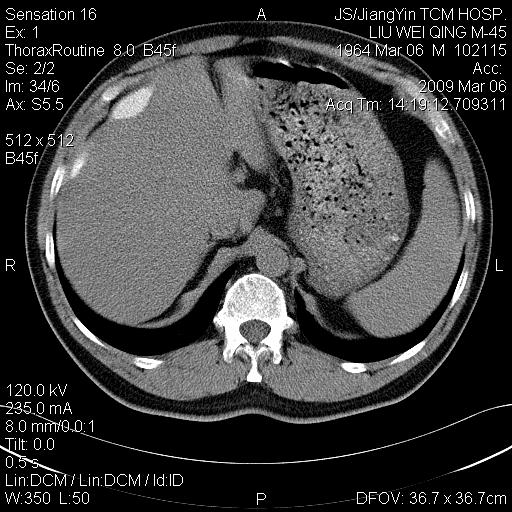

标题: CT18518:胸部扫描时发现肝边缘钙体影。请问是韧带钙化吗? [打印本页]

标题: CT18518:胸部扫描时发现肝边缘钙体影。请问是韧带钙化吗?

没见过。考虑肝内钙化,不象韧带钙化。

考虑肝内右外侧缘两处钙化,原因呢?(血管病变或其它)

考虑肝包膜下陈旧性包裹性积液。

考虑---局限性腹腔积液〔钙乳性〕。    一般多为炎症刺激造成局部钙乳沉着所致。

考虑肝包膜下钙化

考虑肝包膜下钙化.